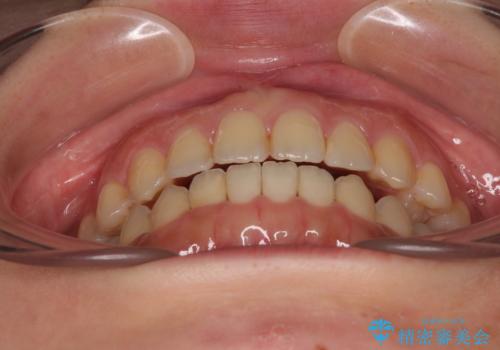

オープンバイトは舌の突出癖により誘発され、治療後も突出癖が残っている容易に後戻りしてしまいます。

治療期間を短縮するためにも、舌突出癖の改善が極めて重要となります。

特にインビザラインではIPRという歯と歯の間を削る処置を多用するため、後戻りによりスペースが生じやすくなるため、治療初期段階での舌のトレーニングが必須となります。